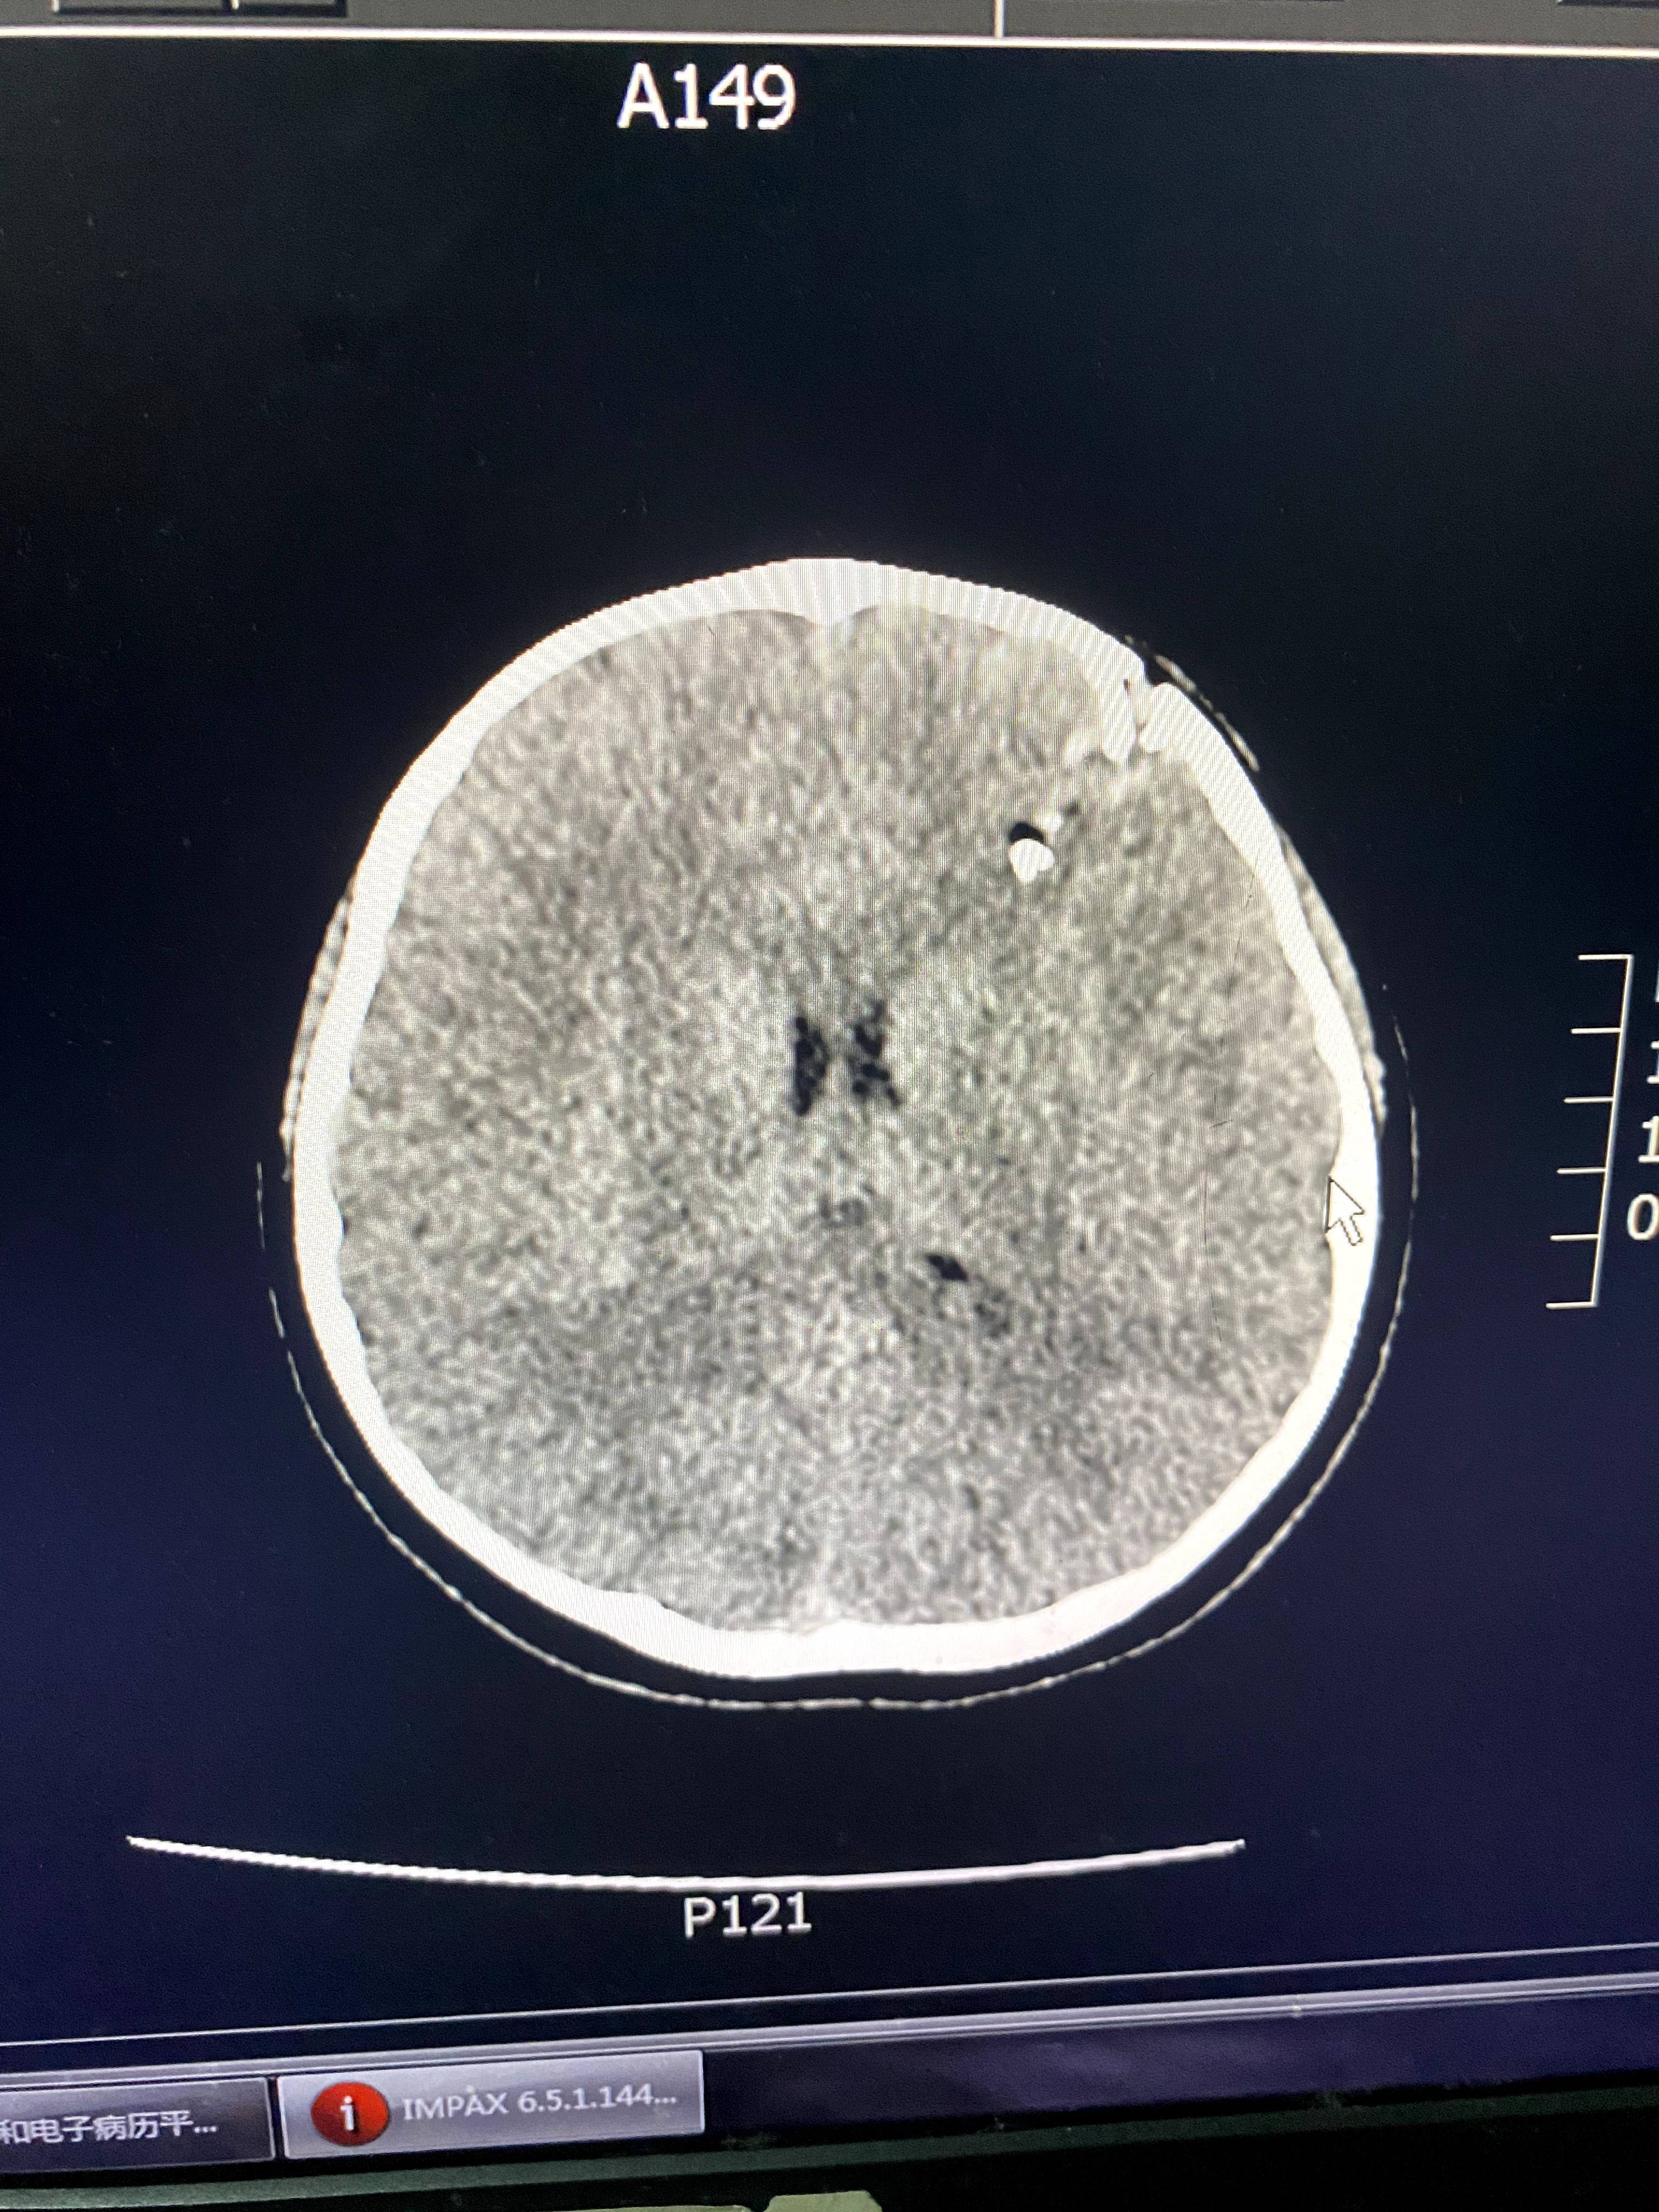

CT显示,星星的颅骨碎裂,颅内有异物。讲述者供图

后来的伤情鉴定结果显示,星星的头面部软组织裂伤,开放性颅骨骨折伴硬脑膜破裂,颅内出血,颅内异物,脑挫裂伤,伤情构成重伤二级。这起事件当年引起了媒体的广泛关注,涉事老师被判处有期徒刑五年,并被禁止从事密切接触未成年人的工作。